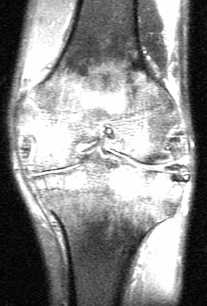

Ювенильный ревматоидный артрит (идиопатический артрит) отличается от ревматоидного артрита у взрослых по клиническому течению и проявлениям на рентгенограммах и МРТ. Типично острое септическое начало, которое длится около 6 недель. При моноартикулярной форме часто поражает коленный сустав. При МРТ коленного сустава видна гипертрофия синовиальной оболочки и выраженный синовит. При полиартикулярной форме страдают также и мелкие суставы.

МРТ коленного сустава. Т2-взвешенная корональная МРТ. Начальный ювенильный ревматоидный артрит.

При МРТ в СПб при МРТ коленного сустава у подростков мы считаем важно дифференцировать различные типы артритов. На ранней стадии может не быть полной картины с характерными рентгенологическими изменениями.